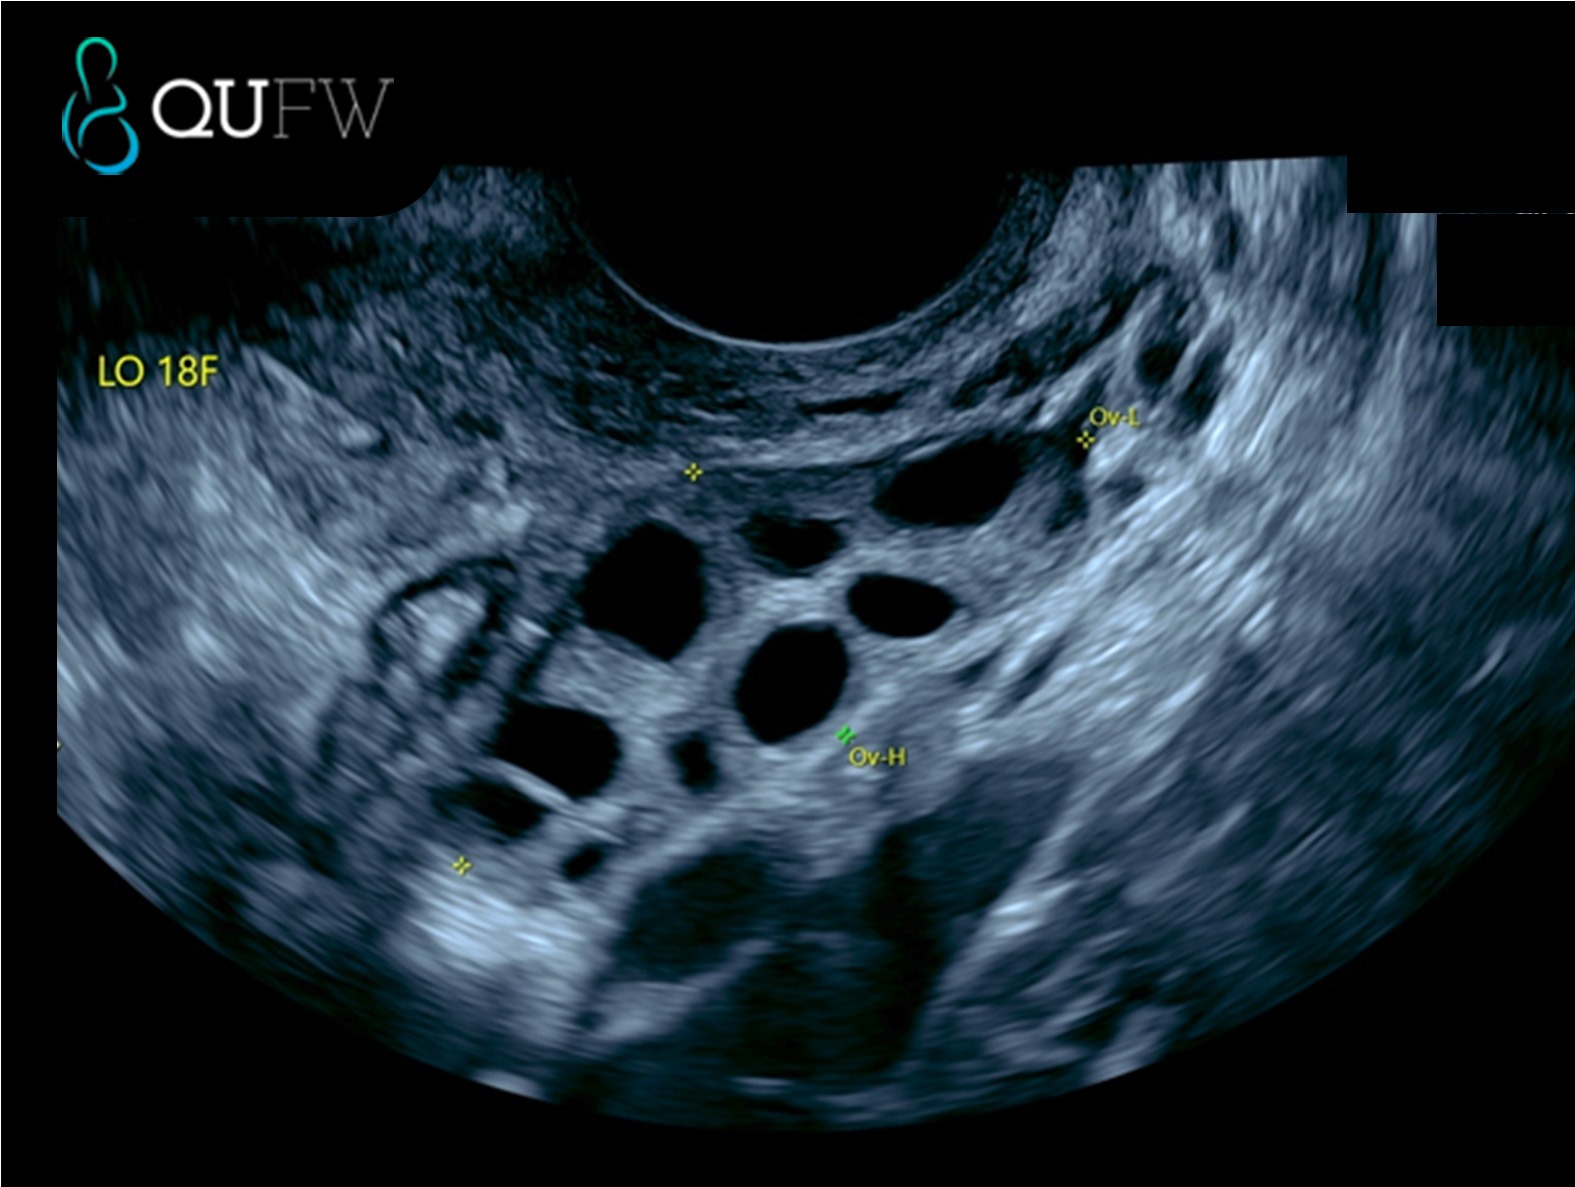

- Ovaries: The scan assesses the size and position of the ovaries, as well as any structural changes. It can identify cysts and monitor their size and appearance. During the assessment, the sonographer will assess the number of antral follicles and follicle sizes. It also can detect solid ovarian masses and help to distinguish between benign and potentially malignant (cancerous) growths.

Left ovary showing follicles